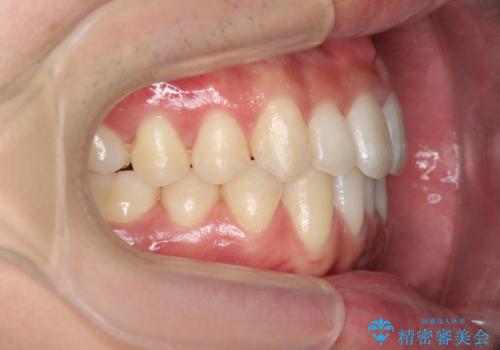

残りは全て天然歯になり、人工物の心配をしなくて済むようになりました。

治療も順調に進み、リファインメントも1回のみで済んでいます。

ブラックトライアングルも少なめで、短期間でしっかり並びました。

下の前歯の歯槽骨が一番薄く、歯肉退縮のリスクがあるため、今回のような1本抜歯も選択肢の一つです。

上の前歯のガタガタも、わずかに歯を削って並べていますので、出っ歯になったりしないようにしています。